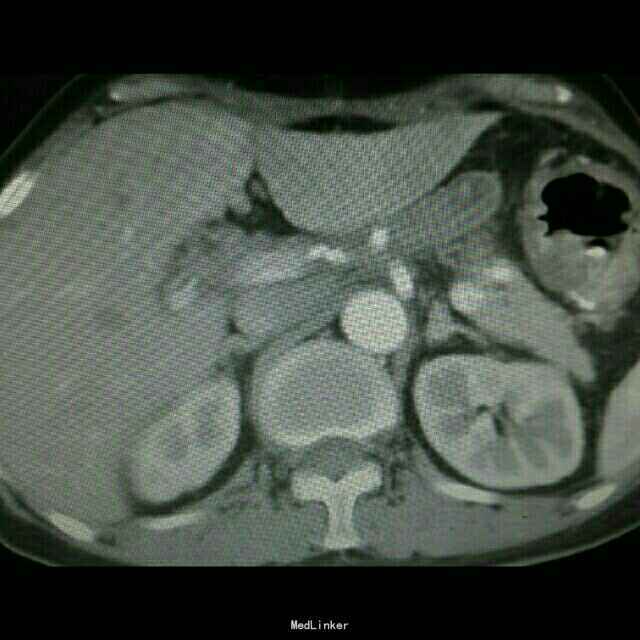

查体:入院后查体腹部平软,未见胃肠型,上腹部正中部可见20cm陈旧性瘢痕,腹部无压痛及跳痛,无肌卫;叩诊鼓音,肝脏及脾脏肋下未及;肝肾区无叩击痛,移动性浊音阴性,肠鸣音弱,1-2次/分。 检查:本次入院后查:WBC:9.2*10^9/L,Na:132mmol/L,余指标基本正常。电子胃镜:胃大部切除术后改变(毕II)吻合口粘膜充血水肿明显,直径约1.2cm,分别尝试进入输入袢及输出袢,见肠腔无明显狭;上腹部增强CT:1胰十二指肠切除术后;2肝脏多发小囊肿;3腹腔内未见明显感染及肿瘤转移征象。上消化道造影:残胃形态、扩张可,未见明显潴留液,蠕动较弱,中远部充盈不佳,胃小肠吻合口宽约1.2cm,未见狭窄及碘水渗漏。胃排空较慢。